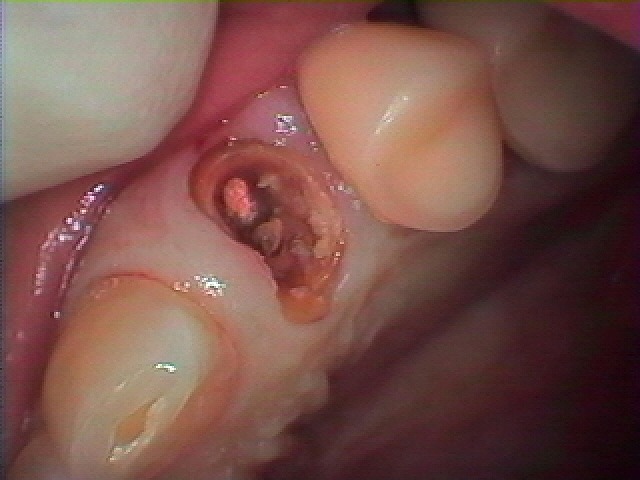

左上のインプラント埋入 即時埋入|お知らせ |広島市安佐南区の歯科医院 左上のインプラント埋入 即時埋入 トップ お知らせ・ブログ お知らせ 左上のインプラント埋入 即時埋入 左上のインプラント埋入 即時埋入 左上が痛いそうです 4番目見たいです 根尖が腫れています パーフォレーションがあり根の治療は難しそうです 被せの中は悪くなっていました 抜歯をお話ししています 抜歯後すぐに埋入していきました 術前のCTになります 術後のCTになります 3ヵ月待っていきます Web診療予約 初めての方へ 選ばれ続ける理由 院内設備について 歯が痛いしみる一般歯科 歯がぐらぐらする歯周病 健康な歯を保ちたい予防歯科 子供の虫歯予防をしたい小児歯科 銀歯をセラミックに審美歯科 白い歯を目指しませんか?ホワイトニング 矯正専門医がいるので安心矯正歯科 抜けた歯を補いたいインプラント・入れ歯 医院案内 スタッフ紹介 メリィハウス歯科クリニックオフィシャルホームページ ラベンダー歯科クリニックオフィシャルホームページ お知らせ・ブログ ホーム 診療科目 一般歯科 歯周病治療 予防治療 小児歯科 審美治療 ホワイトニング 矯正歯科 入れ歯・インプラント マウスピース矯正 初めての方へ 院長・スタッフ 設備紹介 医院案内・アクセス メニューを閉じる